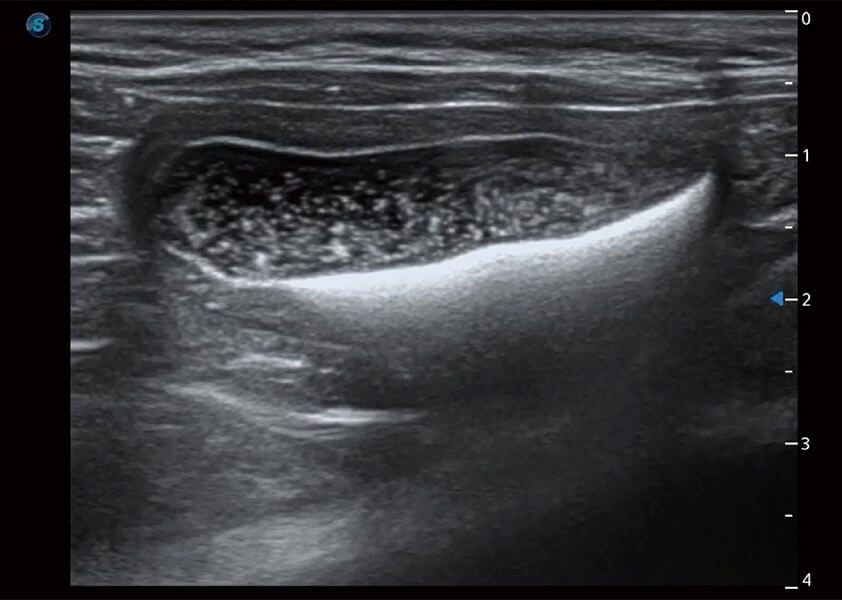

ProPet 60 作为一款高端台式动物超声设备,为动物医生的日常诊断提供了一系列贴合动物临床需求、解决临床实际问题的高级成像功能。凭借全系列高清探头,满足医生对腹部、心脏、生殖、浅表、肌骨等成像的所有需求,切实帮助您提升检查效率,提高诊断信心。